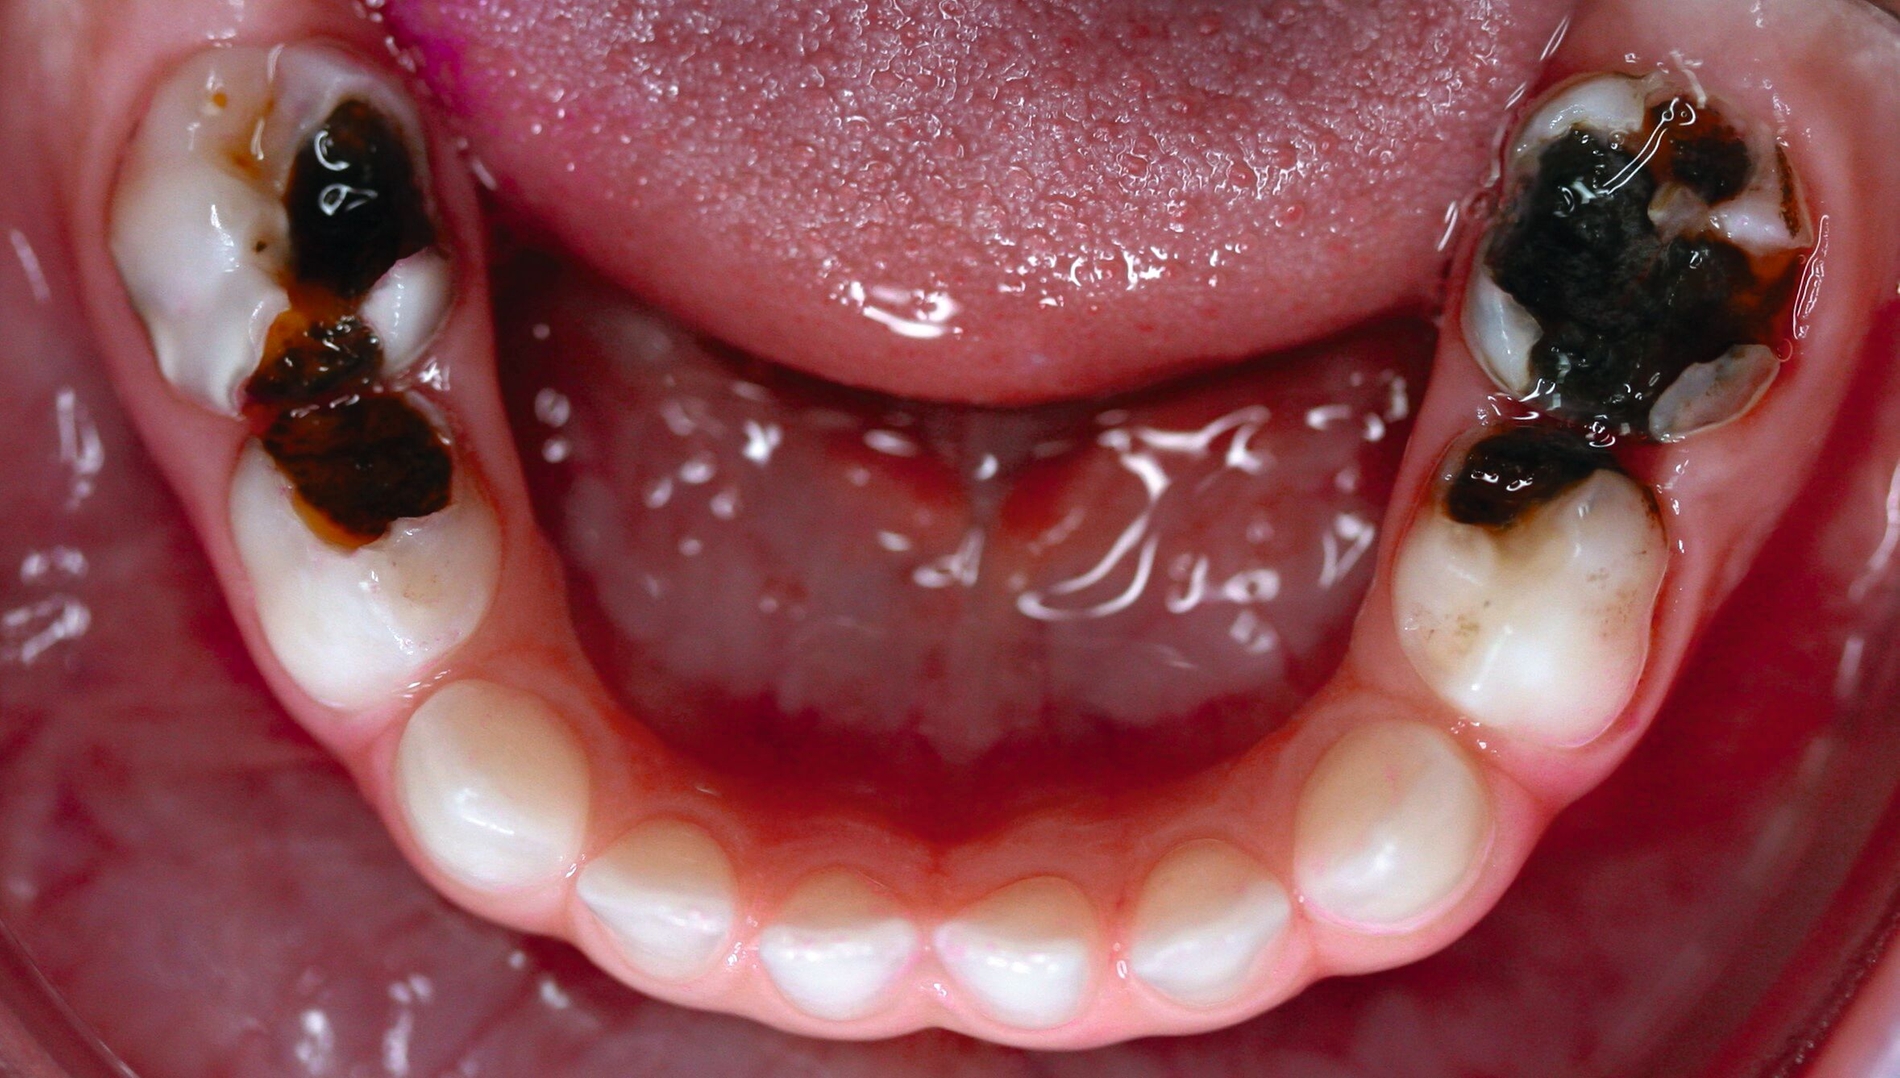

Dank dieses technisch sehr einfachen und zugleich hochwirksamen Ansatzes zur Behandlung kariöser Milchzähne ist es möglich, Dentinkaries ohne Kariesexkavation zu inaktivieren (Abbildungen 4 und 5). Auf diese Weise kann sowohl die Inaktivierung als auch die Remineralisierung kavitierter kariöser Läsionen erreicht werden, selbst wenn die nötige Mitarbeit von Eltern und Kindern beim häuslichen Zähneputzen nicht erreicht wird und/oder die Kooperation für eine konventionelle restaurative Therapie auf dem Zahnarztstuhl (aufgrund eines geringen Alters oder von Angst) ungenügend ist.